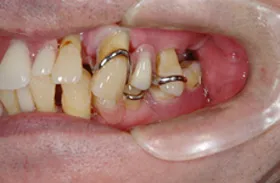

■治療前:上下顎 義歯での食事に満足されていない

■治療後:上下顎 複数本のインプラントを使い固定式で治療

| 主訴 | 現在義歯を使用しているが、しっかりと咬んでなんでもおいしく食事したい |

| 治療方法 | 上下顎 複数本のインプラントを使用しての治療 |

| 治療期間 | 約1年 |

| 通院回数等 | 約20回 |

| 費用 | 約600万円(税込) |

| リスク・副作用 | 術後の腫れ・痛み |